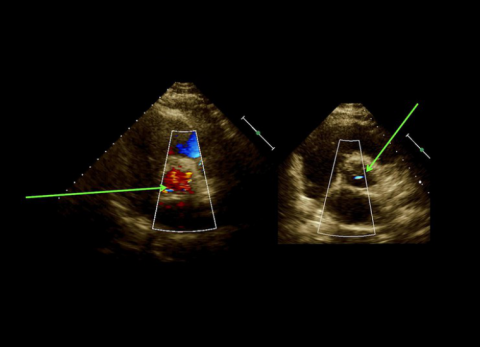

Wideo Echokardiografia. Przypadek 6

prof. dr hab. n. med. Piotr LipiecPacjentka z pogorszeniem tolerancji wysiłku, długotrwałą gorączką i szmerem skurczowo-rozkurczowymi; w wywiadzie narkomania.